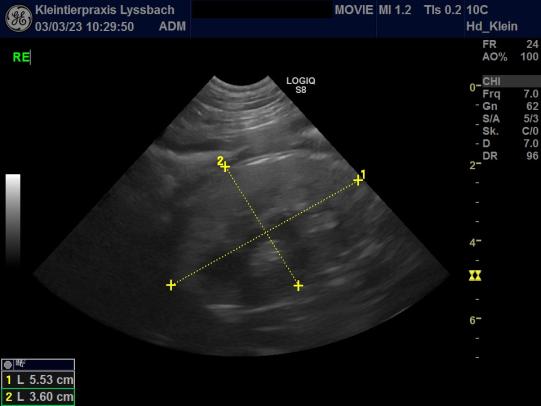

Schon im Alter von knapp 1 1/2 Jahren wurde bei Movie eine Nierenfunktionsstörung festgestellt. Abklärungen deuteten darauf hin, dass sich ihre Nieren wohl nicht korrekt entwickelt hatten (Nierendysplasie). Mit Nierenschonfutter und Medikamenten zur Reduktion des Blut-Phosphorgehaltes zeigte Movie aber bisher abgesehen von der erhöhten Trinkmenge trotz den hohen Nierenwerten eine gute Lebensqualität. Sie zeigte bisher auch keinen durch den Nierenschaden bedingten Bluthochdruck oder übermässigen Eiweissverlust im Urin.